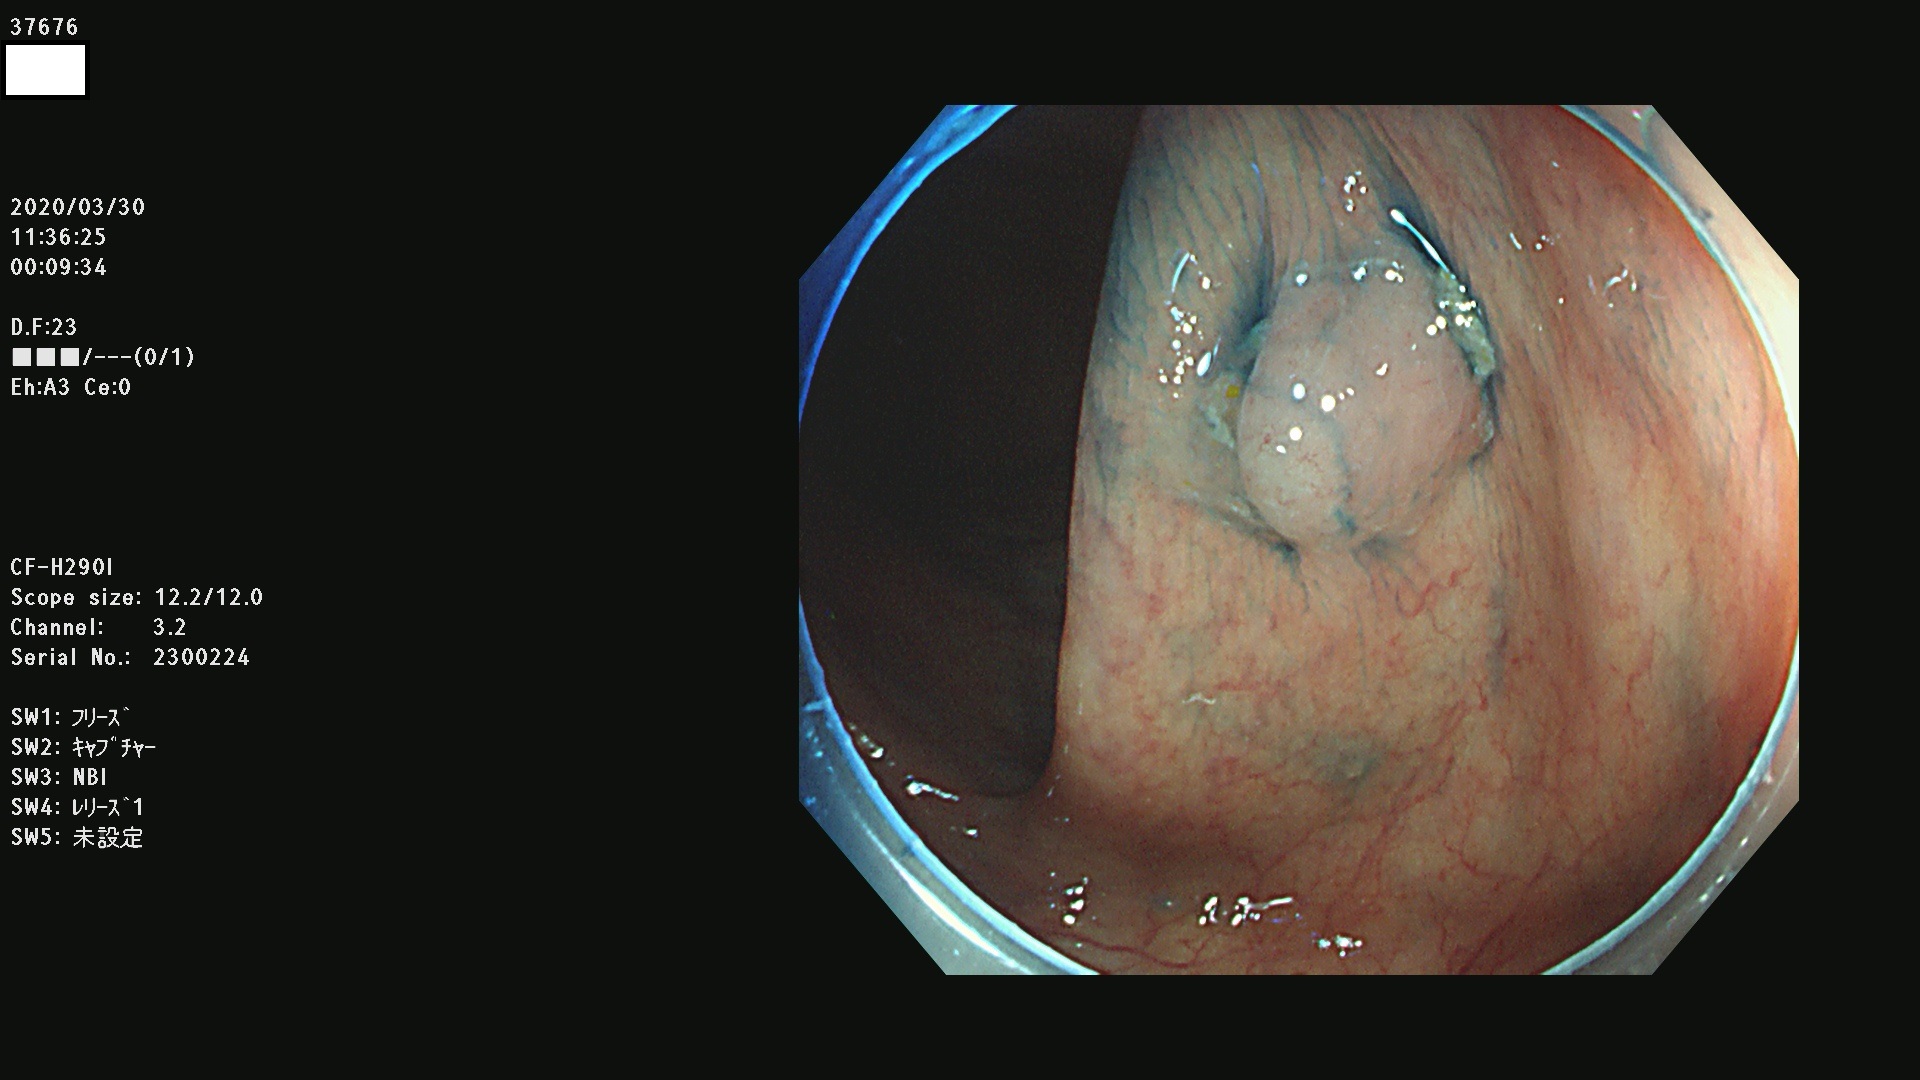

37600 37601 37602 37603 37604 37605 37606 37607 37608 37612 37614 37616 37618 37619 37620 37621 37622(SSAPのみ) 37623(SSAPのみ) 37624 37626 37627 37628 37629 37632 37633 37635 37636(SSAPのみ) 37639 37640 37641 37642 37643 37644 37647(SSAPのみ) 37648 37649 37650 37652 37653 37655 37657 37659 37660 37662 37664 37666 37668(SSAPのみ) 37670 37671 37672 37676 37677 37678 37679 37680 37682 37684 37685(SSAPのみ) 37686 37687 37688 37689 37690 37691 37692(SSAPのみ) 37693 37694 37695 37696 37697 37699

発見困難で危険性の高い平坦型病変(上記100名より抽出)